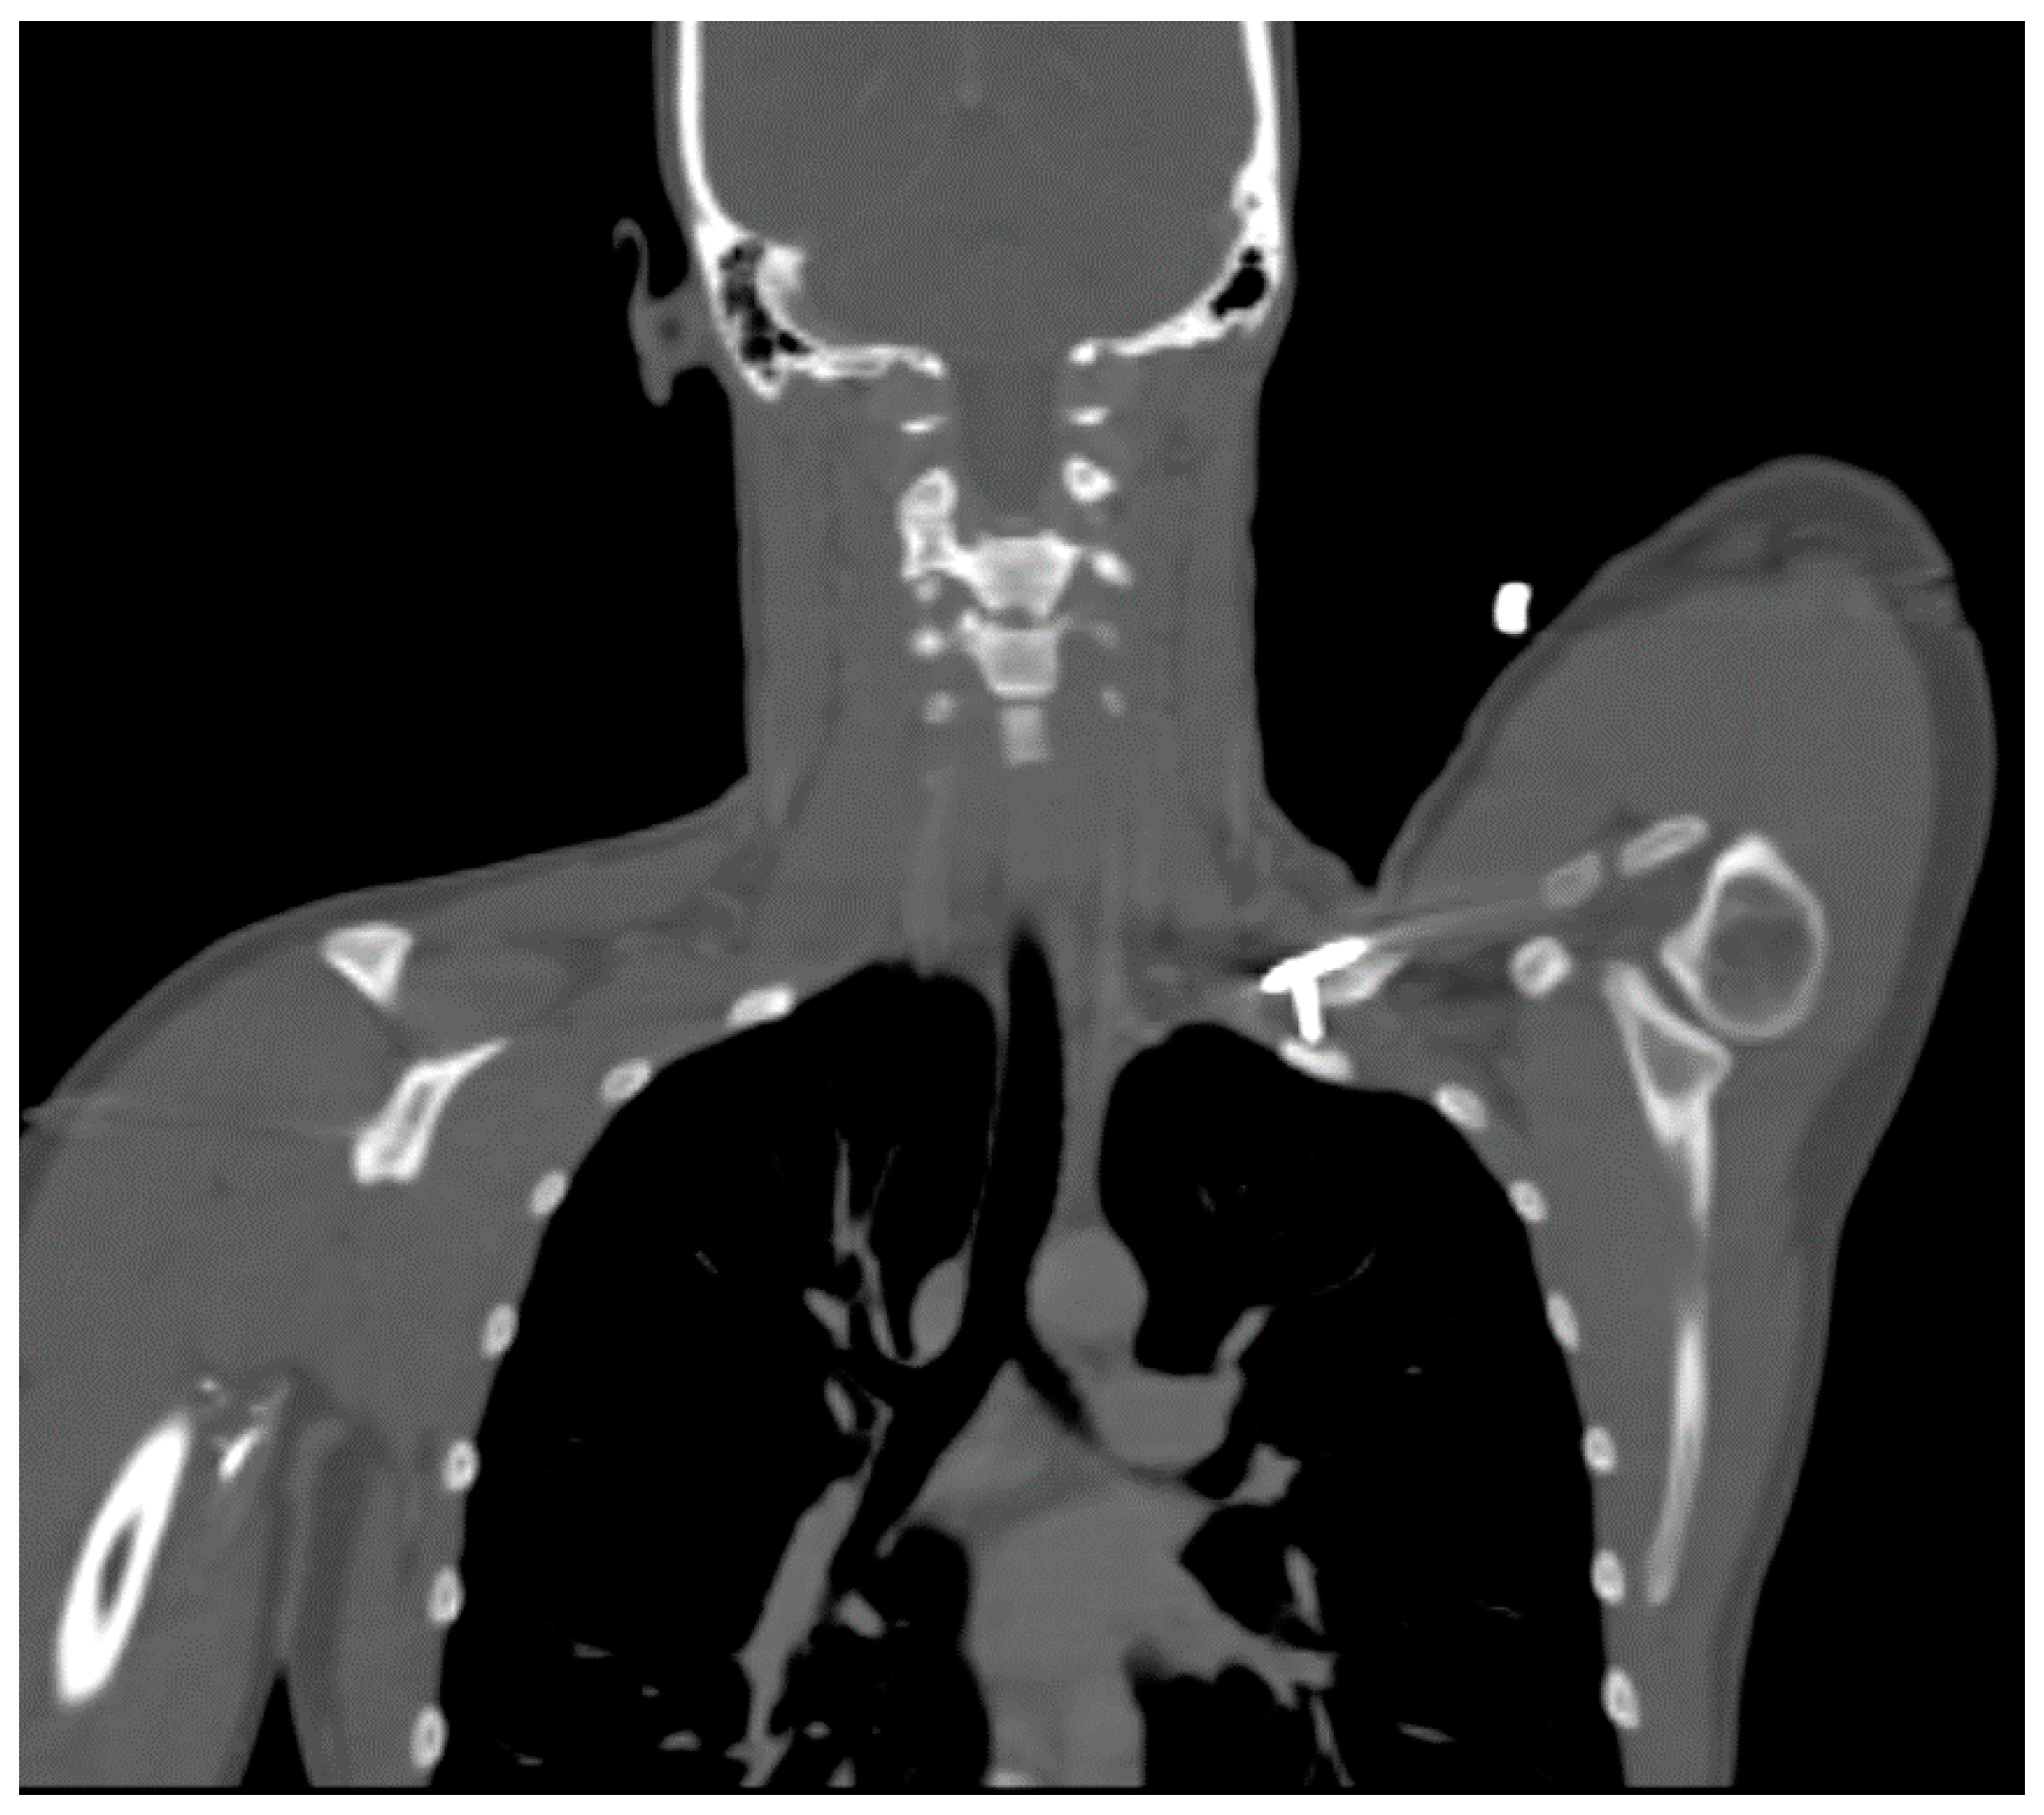

A 27 year-old female who had suffered a left clavicular fracture that was repaired previously presented with left upper extremity numbness and pain for one week. The symptoms occurred spontaneously and were intermittent throughout the week. She experienced no relief with analgesics. She presented to our Emergency Department. Brachial, ulnar and radial pulses were non-palpable. An arterial duplex revealed an occlusive thrombus of the brachial artery at the mid-humerus that appeared to be associated with the patient’s previous clavicular repair (Figure 5). A CT angiogram subsequently revealed a subclavian artery aneurysm adjacent to one of the screws from her prior clavicle repair (Figure 6).

Figure 5.

Arterial thoracic outlet syndrome (ATOS) patient with metal plate and screws after a prior clavicular fracture—the screws are abutting the thoracic outlet.

Figure 6.

CT angiogram demonstrating a screw abutting the thoracic outlet in an ATOS patient with a subclavian artery aneurysm.